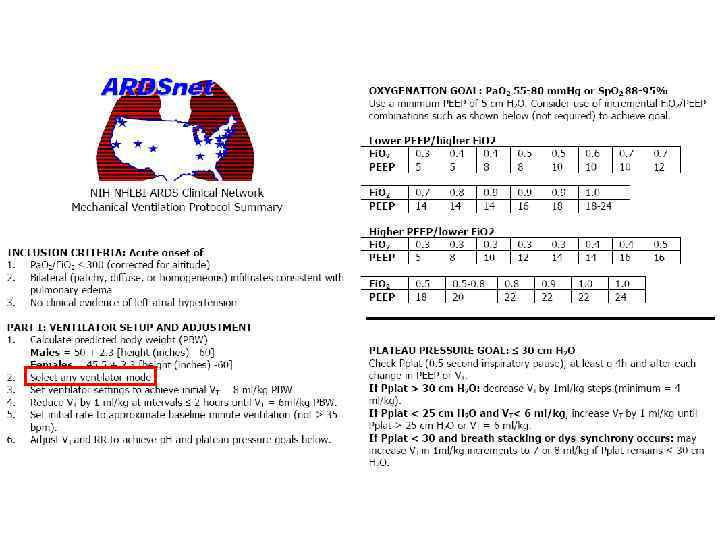

Тактика ARDSnet • Выстави любой режим с начальным ДО 8 мл/кг ПМТ • Выстави ЧД не выше 35 мин-1 для доставки МОД 7 -9 л·мин-1 • Выстави РЕЕР минимум 5 см Н 2 О (возможно, лучше выше…) и FIO 2, достаточное для Sa. O 2 88 -95% или Рa. O 2 55 -80 mm Hg • Титруй FIO 2 до 0, 7, если можно • Не более чем через 4 ч уменьшай ДО до 7 мл/кг, а затем до 6 мл/кг; минимум – 4 мл/кг

Тактика ARDSnet • Выстави любой режим с начальным ДО 8 мл/кг ПМТ • Выстави ЧД не выше 35 мин-1 для доставки МОД 7 -9 л·мин-1 • Выстави РЕЕР минимум 5 см Н 2 О (возможно, лучше выше…) и FIO 2, достаточное для Sa. O 2 88 -95% или Рa. O 2 55 -80 mm Hg • Титруй FIO 2 до 0, 7, если можно • Не более чем через 4 ч уменьшай ДО до 7 мл/кг, а затем до 6 мл/кг; минимум – 4 мл/кг